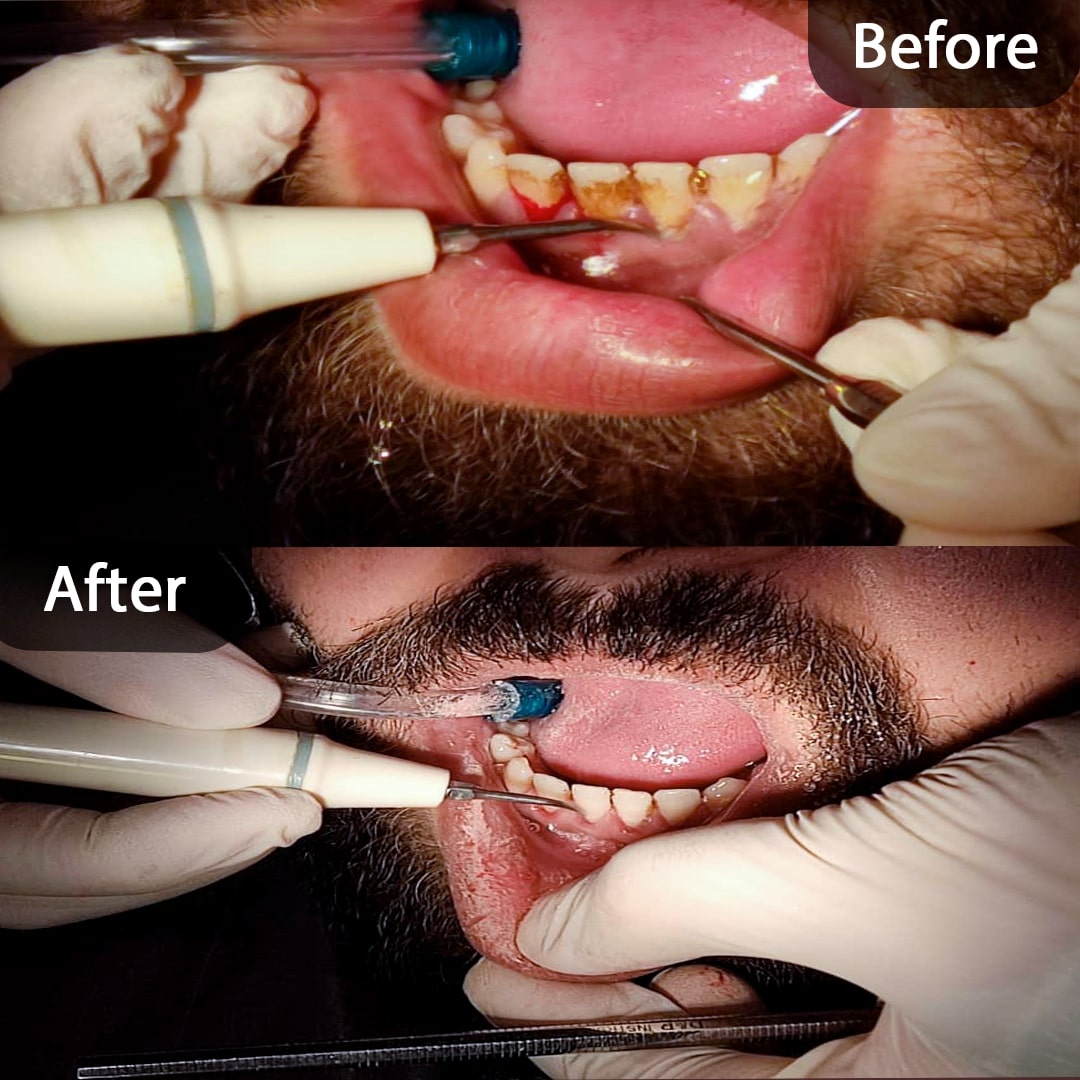

عکس قبل و بعد جرم گیری دندان در کلینیک دندانپزشکی دریای نور